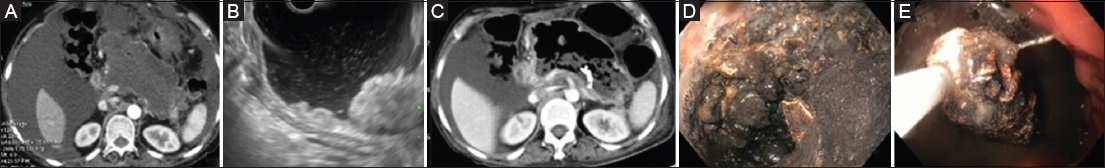

Figure 2 (A) An ill-defined necrotic collection (day 23 or illness). (B) EUS showing solid necrotic debris. (C) CT 3 days after transmural plastic stent placement: liquid content drained out with solid. Necrotic content remaining. (D) Endoscope taken into the cavity after dilation of the transmural tract: significant solid debris present. (E) DEN being performed EUS, endoscopic ultrasound; CT, computed tomography; DEN, direct endoscopic necrosectomy